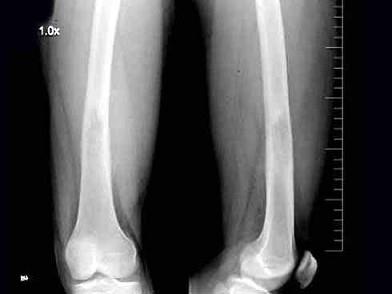

问题 男,23岁,右股骨下段肿胀、疼痛伴发热2个月,摄片如图所示,最可能的诊断是?(?)

选项 A.急性化脓性骨髓炎 B.溶骨性骨肉瘤 C.尤文肉瘤 D.组织细胞增生症 E.以上均不是

答案 C